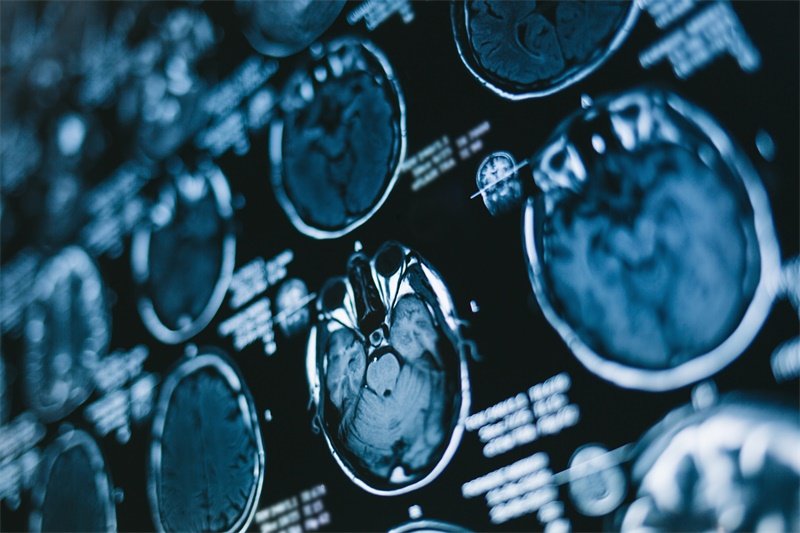

做完磁共振,报告上写着"含铁血黄素沉积"或"含铁血黄素环",大多数人第一反应是懵的,紧接着就开始往坏的方向想:这个是不是新的出血?是不是脑子里又多了一块东西?

在脑子里出现含铁血黄素,往往意味着某个位置曾经有过出血。血液流出来之后,红细胞在原地裂解,铁元素被周围的吞噬细胞摄取、处理,最终以含铁血黄素的形式沉积下来。这个过程通常需要数周甚至更长时间才能完成。